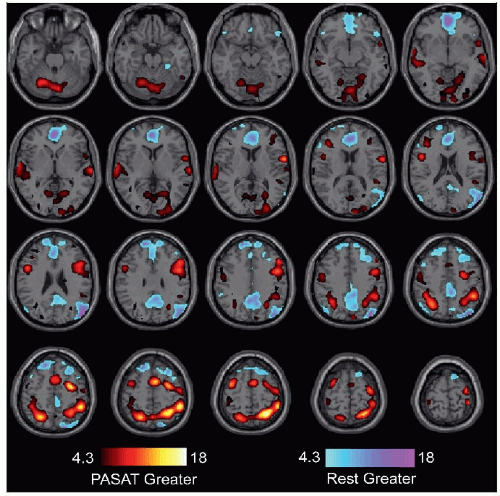

Activation map for an auditory PASAT task is shown for 1 patient. Image is the average of 2 sequences, 6-minutes each. Hot colors show greater activation during the PASAT blocks, and cool colors show greater activation during the rest blocks. Significance is set at q < 0.05, false discovery rate corrected. For the task, the patient listened to a list of single-digit numbers. Each time a new number was heard, she added in her mind the previous 2 numbers. Rest blocks contained no stimuli. Task activation is seen in auditory cortex, dorsolateral prefrontal cortex, intraparietal sulcus, medial cerebellum, frontal eye fields, and supplementary motor area. |